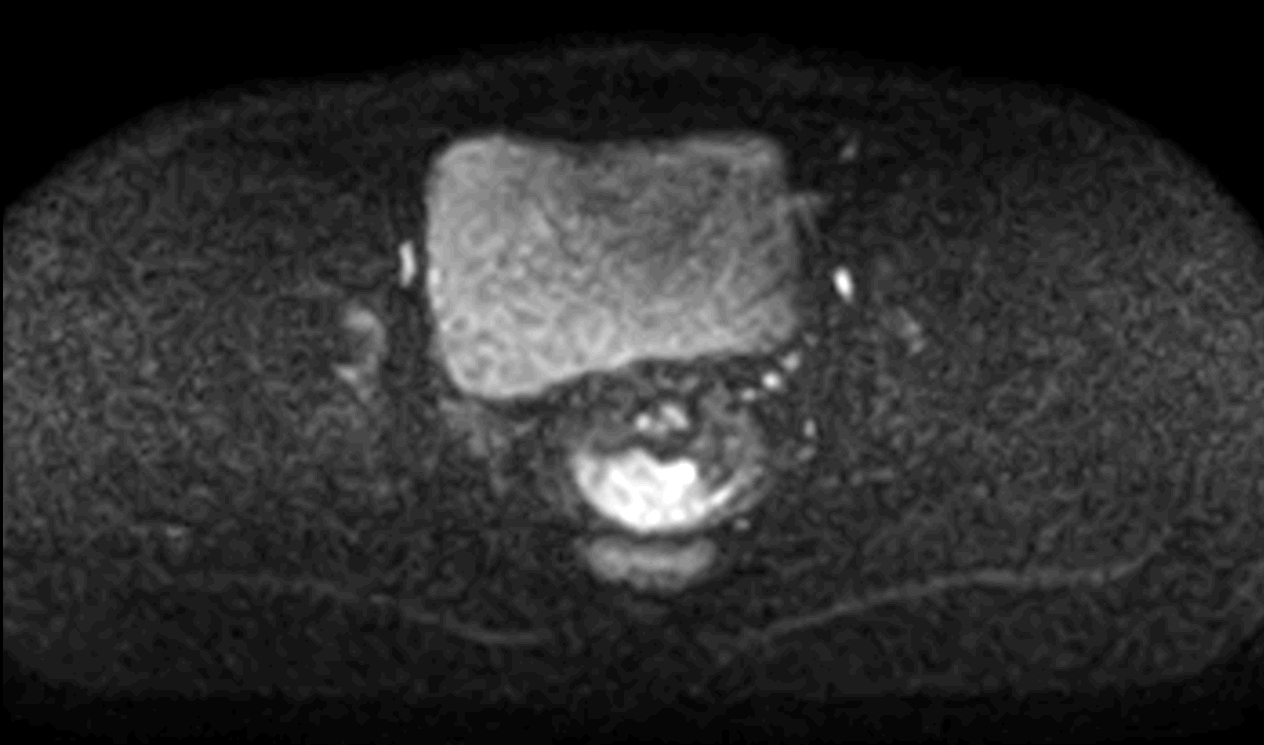

Axial DWI (ADC) mid

-